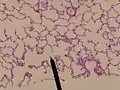

![]() An alveolus showing an alveolar duct | |

human alveolar duct